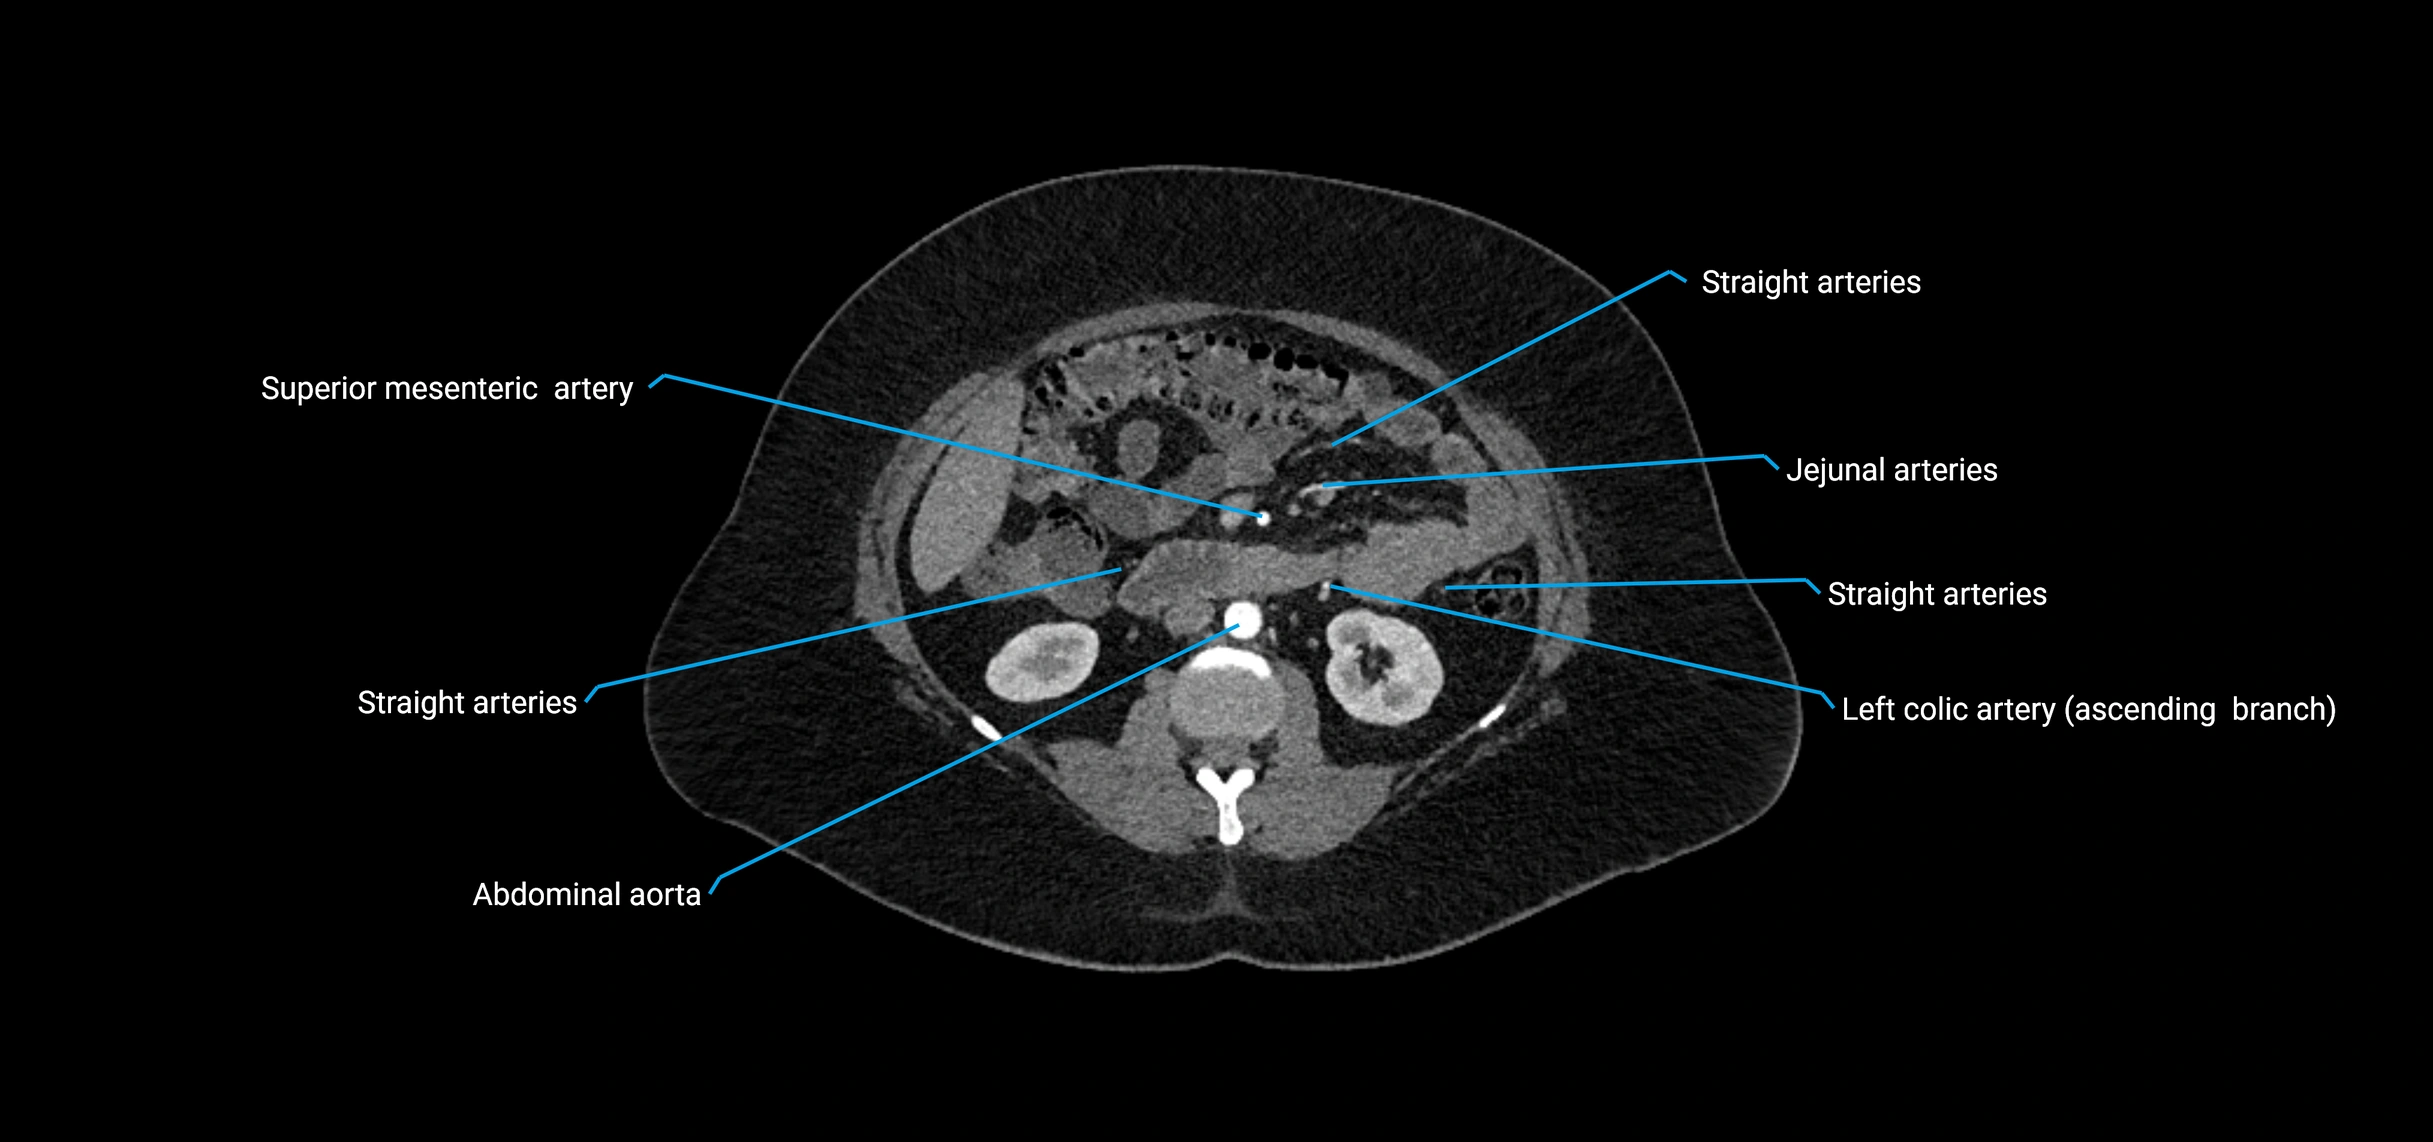

Contrast-enhanced CT (CTA):

• Gold standard for abdominal aortic imaging

• Provides excellent detail of lumen, wall, aneurysm, thrombus, and branch vessels

• Multiplanar and 3D reconstructions help in aneurysm measurement, stent graft planning, and dissection evaluation

• Detects acute rupture, traumatic injury, or occlusion with high sensitivity